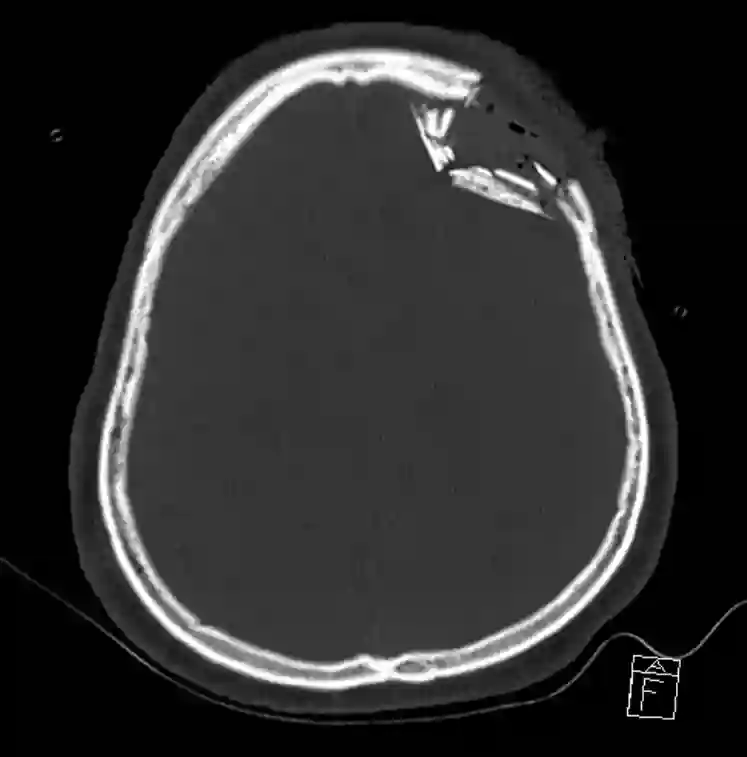

Impressionsfraktur im CT

Impressionsfraktur frontal links im axialen CT.